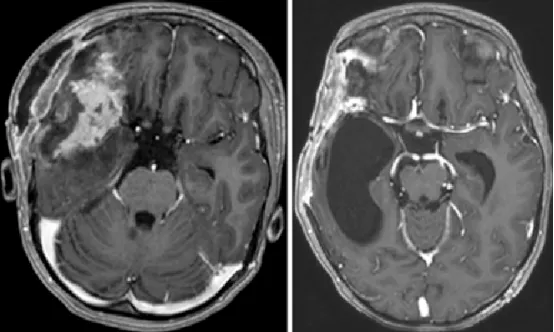

图4. 左:开颅术后第1天轴位T1增强MRI,显示肿瘤次全切除术后改变及周围脑软化;右:术后3个月轴位T1增强MRI,见侧裂远端肿瘤残留,右侧颞角扩大,已行脑室-腹腔分流术。